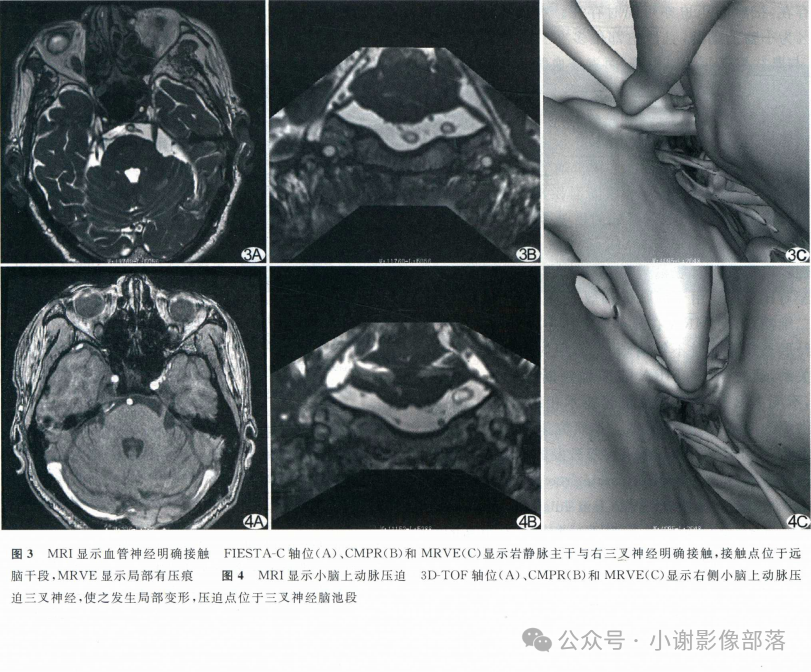

在轴位MR图像上观察并准确辨识出相应的神经和血管,常规的FSE T2WI也可以看到这些颅神经和血管,但不够清晰,尽量还是在更专业的3D重T2WI序列或3D B_FFE序列上观察,如下图↓

MR是目前诊断面肌痉挛及三叉神经痛的主要检查手段。

T2-TSE3D-RST-TRA成像是重T2成像,脑脊液呈高信号,三叉神经,面听神经和血管在脑脊液的高信号衬托下呈低信号可清晰显示,即使周围很小的血管分支也可能成像。

此外,T2-TSE3D-RST-TRA能对静脉以低信号成像,而且无须造影剂,通过多层面分析可确定压迫血管的来源,与常规磁共振技术相比不仅扫描速度成倍提高,并且通过三维薄层技术弥补对比度和分辨率的损失,获得高分辨率、高信噪比的图像,是检查脑神经和血管成像的最佳技术。